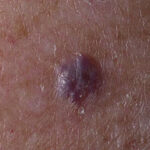

NICH are also present at birth, but usually flatter than RICH, presenting as a well-circumscribed round to oval, slightly indurated or raised soft-tissue mass with overlying telangiectasias and a rim of pallor .

Both NICH and RICH are high-flow vascular anomalies, often showing arteriovenous micro-fistulas on Doppler interrogation. Some cases of RICH involute only partially, and the residual tumor resembles NICH, supporting the concept that RICH and NICH may be variants of each other.